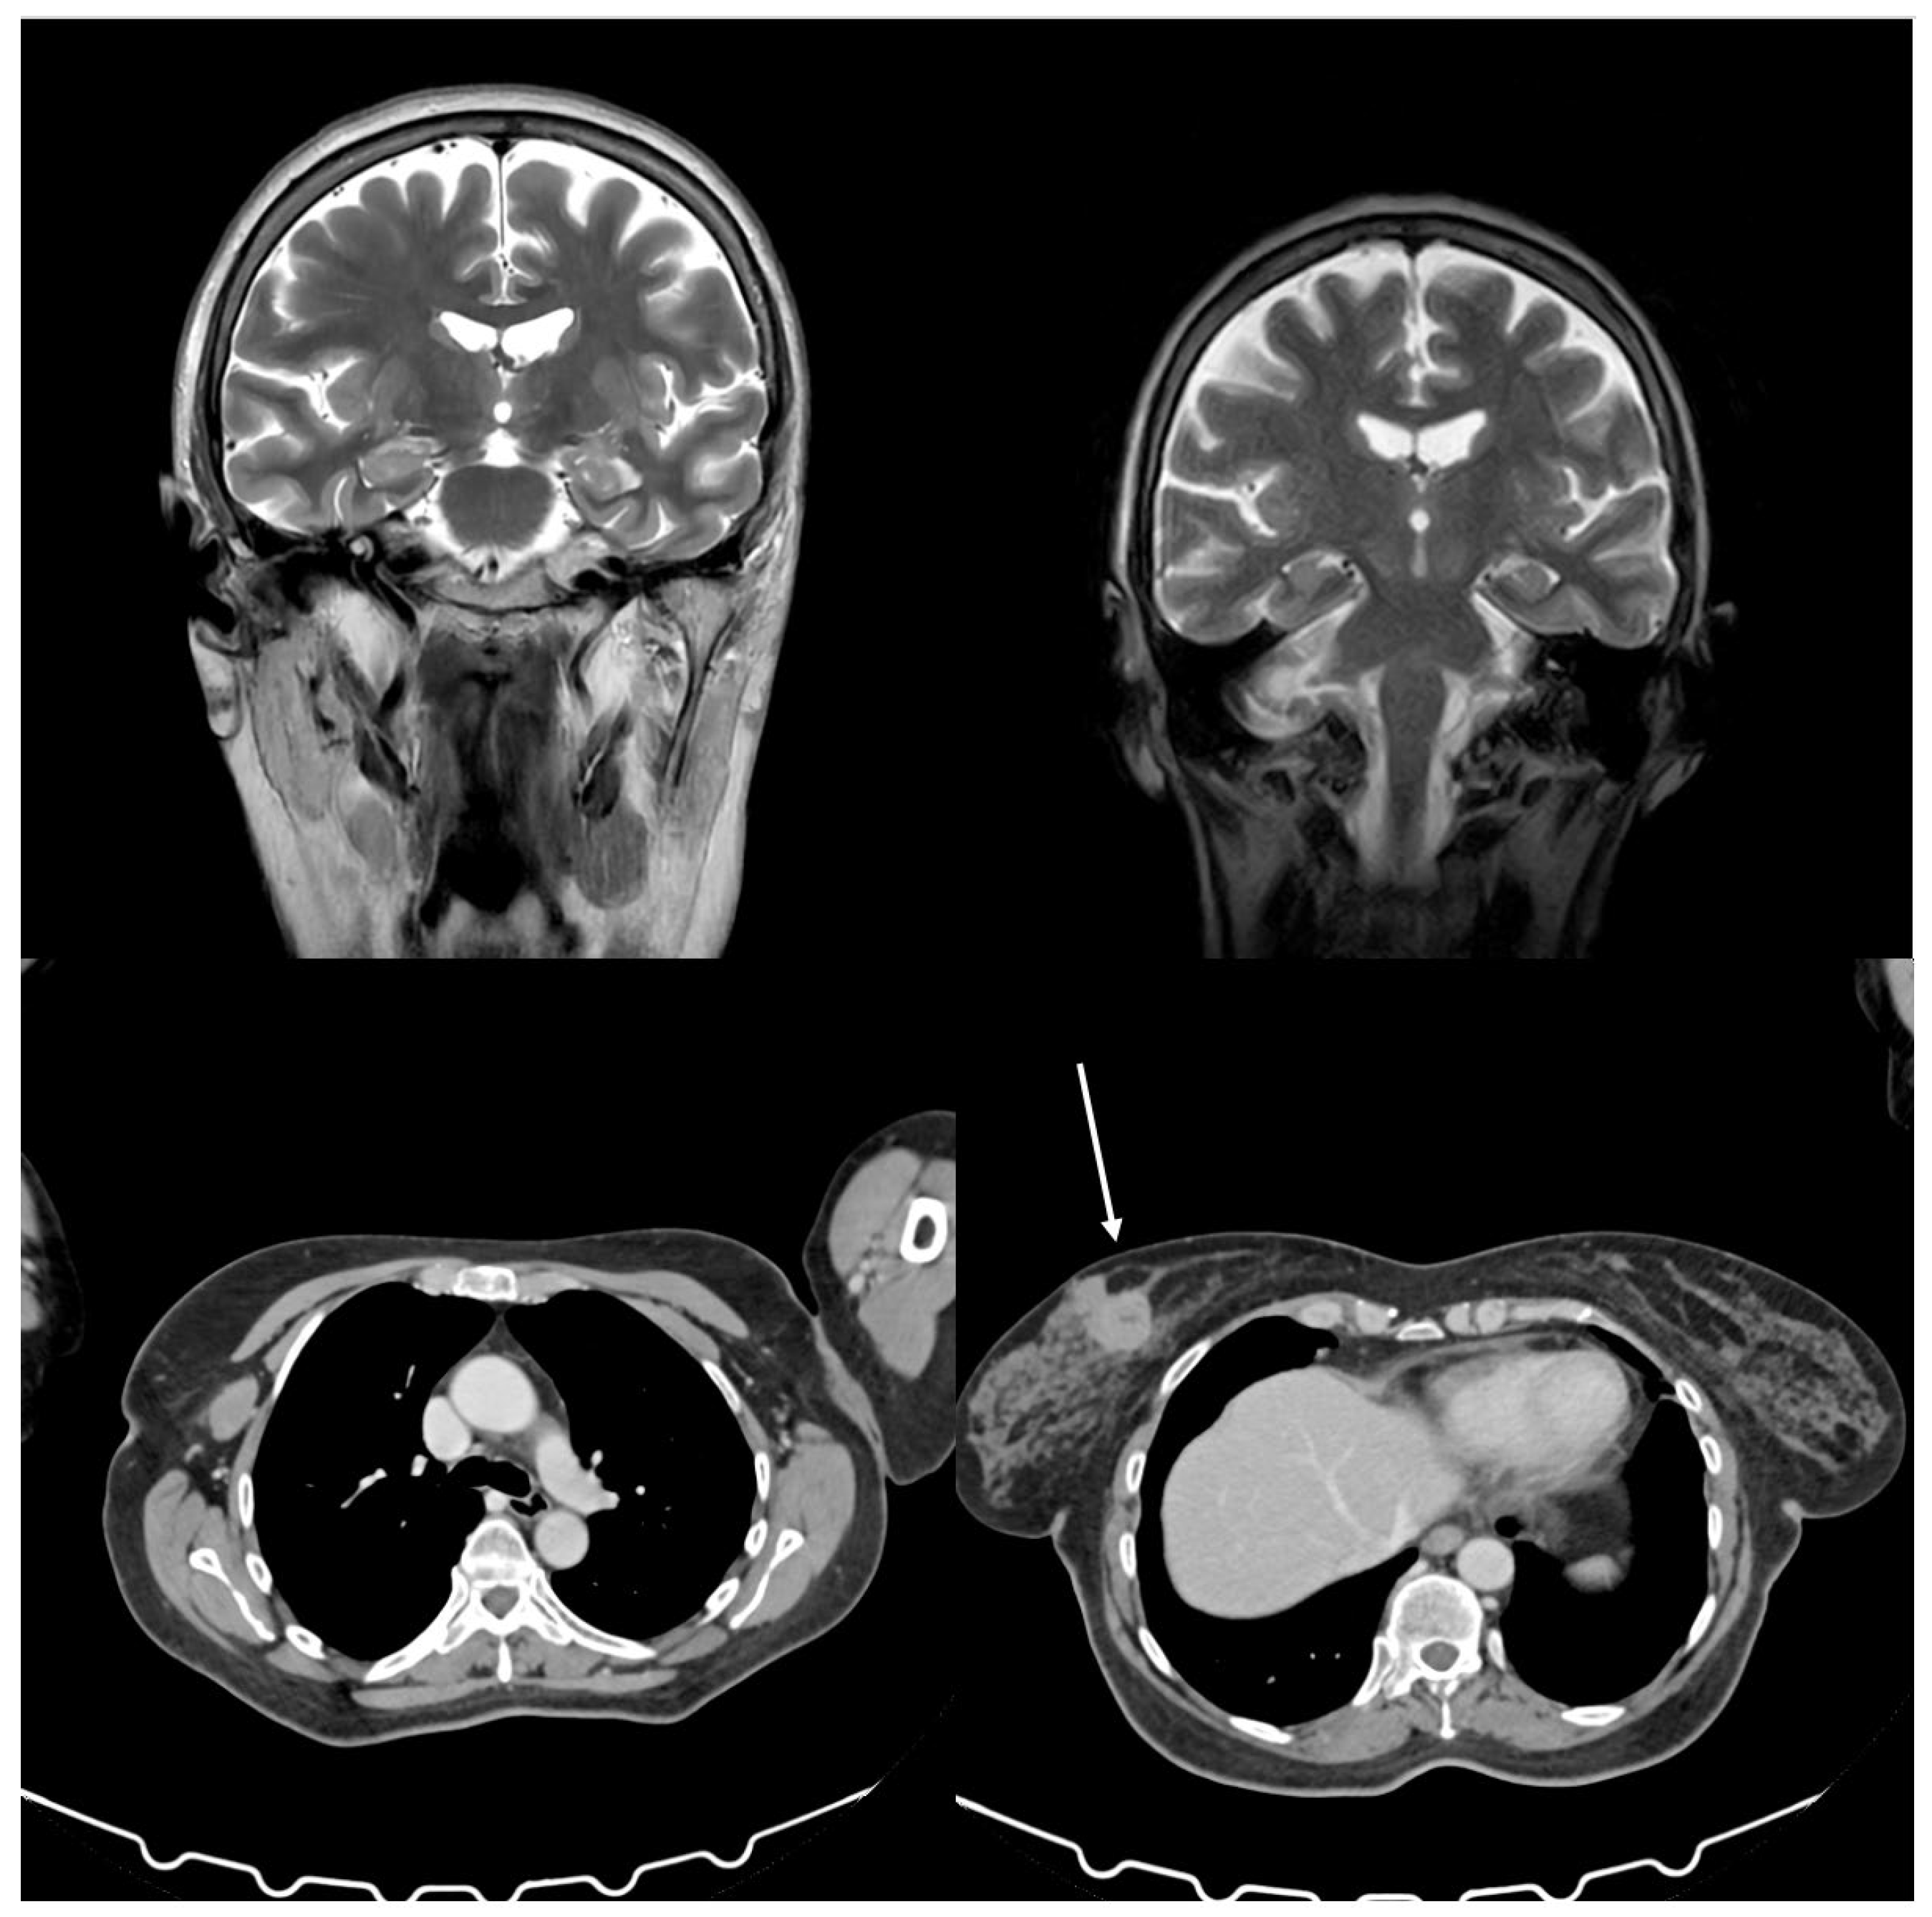

On June 1, 2024, a 58-year-old Caucasian woman was admitted to a secondary oncology center for suspicious breast cancer and complex neurological symptoms, which were initially interpreted as depression, antidepressant overdose, or a neurological functional disorder by various community neurologists and psychiatrists. Figure 1 shows patient’s history timeline. She was treated with sertraline, lamotrigine, and benzodiazepines without any clinical benefit. Her medical history was positive for hypertension and depression, treated with duloxetine, and negative for diabetes, allergies, and any other significant comorbidities. Mammography and breast sonogram revealed a spicular mass measuring 3.3 x 2.6 cm located in the internal upper quadrant of the left breast. A total body CT scan confirmed the mass in the left breast, the presence of several lymph nodes in the homolateral axilla measuring 2.7 cm without distant metastases, and a mass in the right kidney consistent with an angiomyolipoma (Figure 2). An MRI confirmed the findings in the breast and kidney (Figure 2). A biopsy of the breast lesion and axillary nodes showed poorly differentiated ductal infiltrating carcinoma of the left breast, with 95% positive estrogen receptors, 12% positive progesterone receptors, HER-2 2+, FISH not amplified, Ki67 at 50%, E-cadherin positive, CK5 positive, and no vascular or perineural invasion. The cardiology function evaluation was normal. The breast unit multidisciplinary team concluded that the patient was unfit for neoadjuvant chemotherapy due to neurological symptoms and referred her back to the surgeon for upfront surgery. The family then sought a second opinion at the University Hospital of Palermo, Italy, where the patient was admitted in the same month with a suspected paraneoplastic neurological syndrome. Upon admission, the patient complained of vertigo, nausea, vomiting, and rigidity in all four limbs that had occurred ten months prior and progressively worsened. During the neurological evaluation, the patient presented with bilateral eyelid ptosis, opsoclonus, jaw dystonia, and hypertonia, more severe in the upper limbs, as well as exaggerated osteotendinous reflexes in both upper and lower limbs, bilateral Hoffmann sign, myoclonus in the upper limbs, bilateral pes cavus, and pseudo dysmetria. Only the hypertonia in the limbs and axis improved after administering 10 mg of intramuscular diazepam. Repetitive nerve stimulation, brain scan with DAT-Scan, electrocardiogram, and supra-aortic doppler were unremarkable. Nerve conduction studies and needle electromyography revealed bilateral carpal tunnel syndrome and radiculopathy at C8-T1. In contrast, brain and cervical cord resonance imaging (NMR) highlighted bilateral mild atrophy in the temporal and frontal lobes (Figure 2). Antibodies against acetylcholine receptor (AChR), muscle-specific kinase (MuSK), and GABA decarboxylase (GAD) were within the normal range. Blood tests and a lumbar puncture were performed, revealing serum CA 15-3 at 45 U/mL, neuron-specific enolase at 59.2 μg/L, ANA 1:160 (speckled pattern), low vitamin B12, high heavy chain neurofilaments, and 80 cells in the cerebrospinal fluid. The final diagnosis was invasive ductal carcinoma and OMS with positivity for anti-Ri antibodies. According to the ECOG scale, medical oncologists classified the patients with a performance status of 2 due to the neurological picture rather than cancer. The patient became increasingly drowsy with an evident walking deficit. On August 19, 2024, a second CT scan showed no vascular damage or metastasis in the CNS and stable disease in the breast. The second oncologist at the University Hospital prescribed anastrozole at 1 mg/day based on histology, positive hormonal receptors status, and post-menopausal status reserving the use of chemotherapy in case of improvement of the general conditions. The multisciplinary team approved therapeutic strategy and scheduled surgery.

Figure 2. Brain nuclear magnetic resonance showing no metastases, and a CT scan of the thorax and the abdomen showing a mass in the breast cancer (white arrow) and no distant metastases.